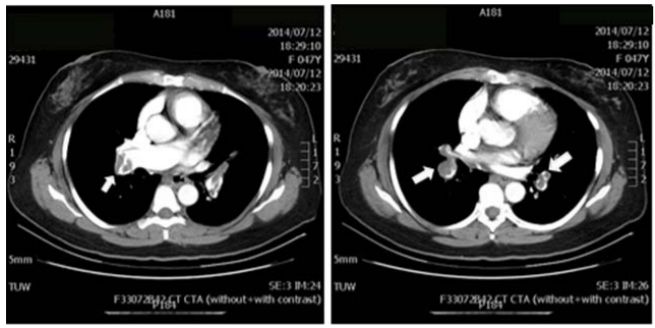

5. 病人男性59歲於午夜24時,突因胸悶並有牙床緊疼,乃直往急診部求診,時病人之T/P/R = 35.1/51/18, BP 137/74 mmHg; 理學檢查,未見任何異常。病史追尋,本病人曾經醫師確定高血壓、高脂血、糖尿病及攝護腺肥大,唯僅只服用Bisoprolol 2.5 mg/day。經緊急檢查:其心電圖及胸部X光顯示如圖:生化檢查: CK,96 U/L;CK-MB,20 U/L;TnI <0.0012 ng/ml;Sugar 252 mg/dL; Na,137 mmol/L; K, 3.7 mmol/L; TG,182 mg/dL and Total cholesterol, 222 mg/dL ; 血液檢查: Hb,13.9 g/dl; Platelet, 203 K/uL; WBC,9.45 K/uL; Cre,1.3 mg/dL 請問本病人最可能的急診診斷是:

(A) Printzmetal's angina (B) Aortic dissection (C) Acute anterior myocardial infarction (D) Hypertension (E) Acute periodontitis disease